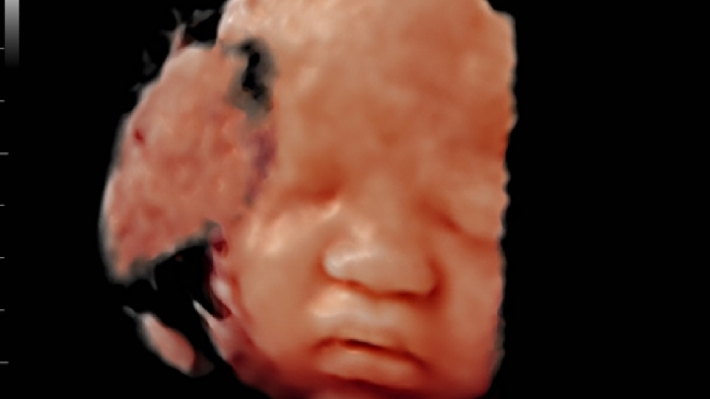

УЗИ-аппарат Mindray DC-70 — это современная ультразвуковая система экспертного класса, предназначенная для проведения диагностических исследований в различных областях медицины, включая кардиологию, акушерство и гинекологию, абдоминальные и сосудистые исследования. Аппарат сочетает высокое качество изображения с широким набором функциональных возможностей, что делает его эффективным инструментом для диагностики.

• Многофункциональность: Поддержка различных режимов сканирования, включая 2D, 3D/4D, цветное допплеровское картирование и другие, позволяет использовать аппарат для широкого спектра медицинских задач;

• Smart OB™ — программа автоматического расчета основных акушерских показателей;

• iLive™ — технология 3D/4D-визуализации с функцией постобработки изображений;

Изображения